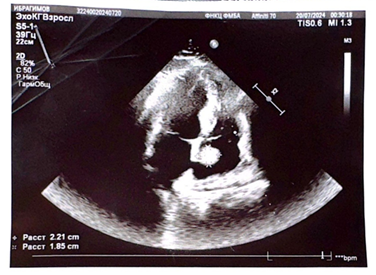

Exokardioqrafik müayinə zamanı sağ qulaqcıqda arakəsmə nahiyəsində 2.21 X 1,85 ölçüdə az hərəkətlı törəmə qeyd edilir. Ürək boşluqları böyüməyib. Diastolik funksiya pozulmayıb. Qlobal sistolik funksiya saxlanılır. . Xəstəyə Moskvada təcili yardım maşını çağrılıb və hospitalizasiya olunub. EKQ şəkil 1.

Nəticə: Sağ qulaqcıq daxili törəmə 2.8x2.5 cm ölçüdə hamar kənarları olan sağ qulaqcıq divarına fiksə olunmuş ayaqcıqlı törəmə izlənilir (ayaqcığın ölçüsü 12mm) Kardiocərrahın baxışı aparılmış, xəstəyə sağ qulaqcığın miksoması diaqnozu qoyulmuş və cərrahi müdaxilə təyin edilmişdir. Müalicə müddətində Holter müayinəsi aparılmışdır. Xəstədə sinus ritmi minimal UVS-48 maksimal 132 olmuşdur. Evə yazılarkən xəstəyə Apixaban 5mgX2 dəfə. Rivaroksoban20mg, Dabigatran (prodaksal) 150mgX2 dəfə üç ay müddətinə, Propofenon 150mgX2 dəfə, Rozulip plus axşam yeməkdən sonra təyinatı ilə təkrar ambulator müayinəyə göndərilmişdir. Xəstənin qanının ümumi analizi, biokimyəvi analizi, sidiyin ümumi analizində dəyişiklik qeyd edilmir. 8/VIII/2024-cü il tarixində xəstə səyrici aritmiya və boğulma şikayəti ilə C.Abdullayev adın Elmi-Tədqiqat Kardiologiya İnstitutuna müraciət etmiş; exoKardioqrafik, elektrokardioqrafik, laborator müayinələr aparılmışdır.

Sağ qulaqcıq daxilində olan törəmənin exo müayinə zamanı tromb üçün xarakter olmayan düz xətt şəkilində olan görüntü və bütün anamnestik məlumatlar və aşağı ətraf venalarında aparılan əməliyyat və bundan sonra xəstədə paroksizmal səyrici aritmiya tutmaları və boğulmaların olması bizdə xəstədə sağ qulaqcıq daxilində aşkar edilən törəmənin genezini müəyyən etmək üçün kardio cərrahın müayinəsinə göndərilır. Xəstəyə cərrahi müdaxilə qərarı verildi.Əməliyyat zamanı xəstədə 2-yə qatlanmış 20cm- ə qədər ölçüsü olan yad cisim (kateter) aşkar edildi – xaric edildi. Xəstədə sağ qulaqcıqda olan kateterin ortadan 2-yə qatlanmaqla sağ qulaqcıq divarına sancıldığı və ətrafına qan elementlərinin tromblaşması nəticəsində şarvari bir şəkil aldığı müəyyən edildi. Xəstənın bir illik müşahidəmiz dövründə heç bir şikayəti olmamışdır.